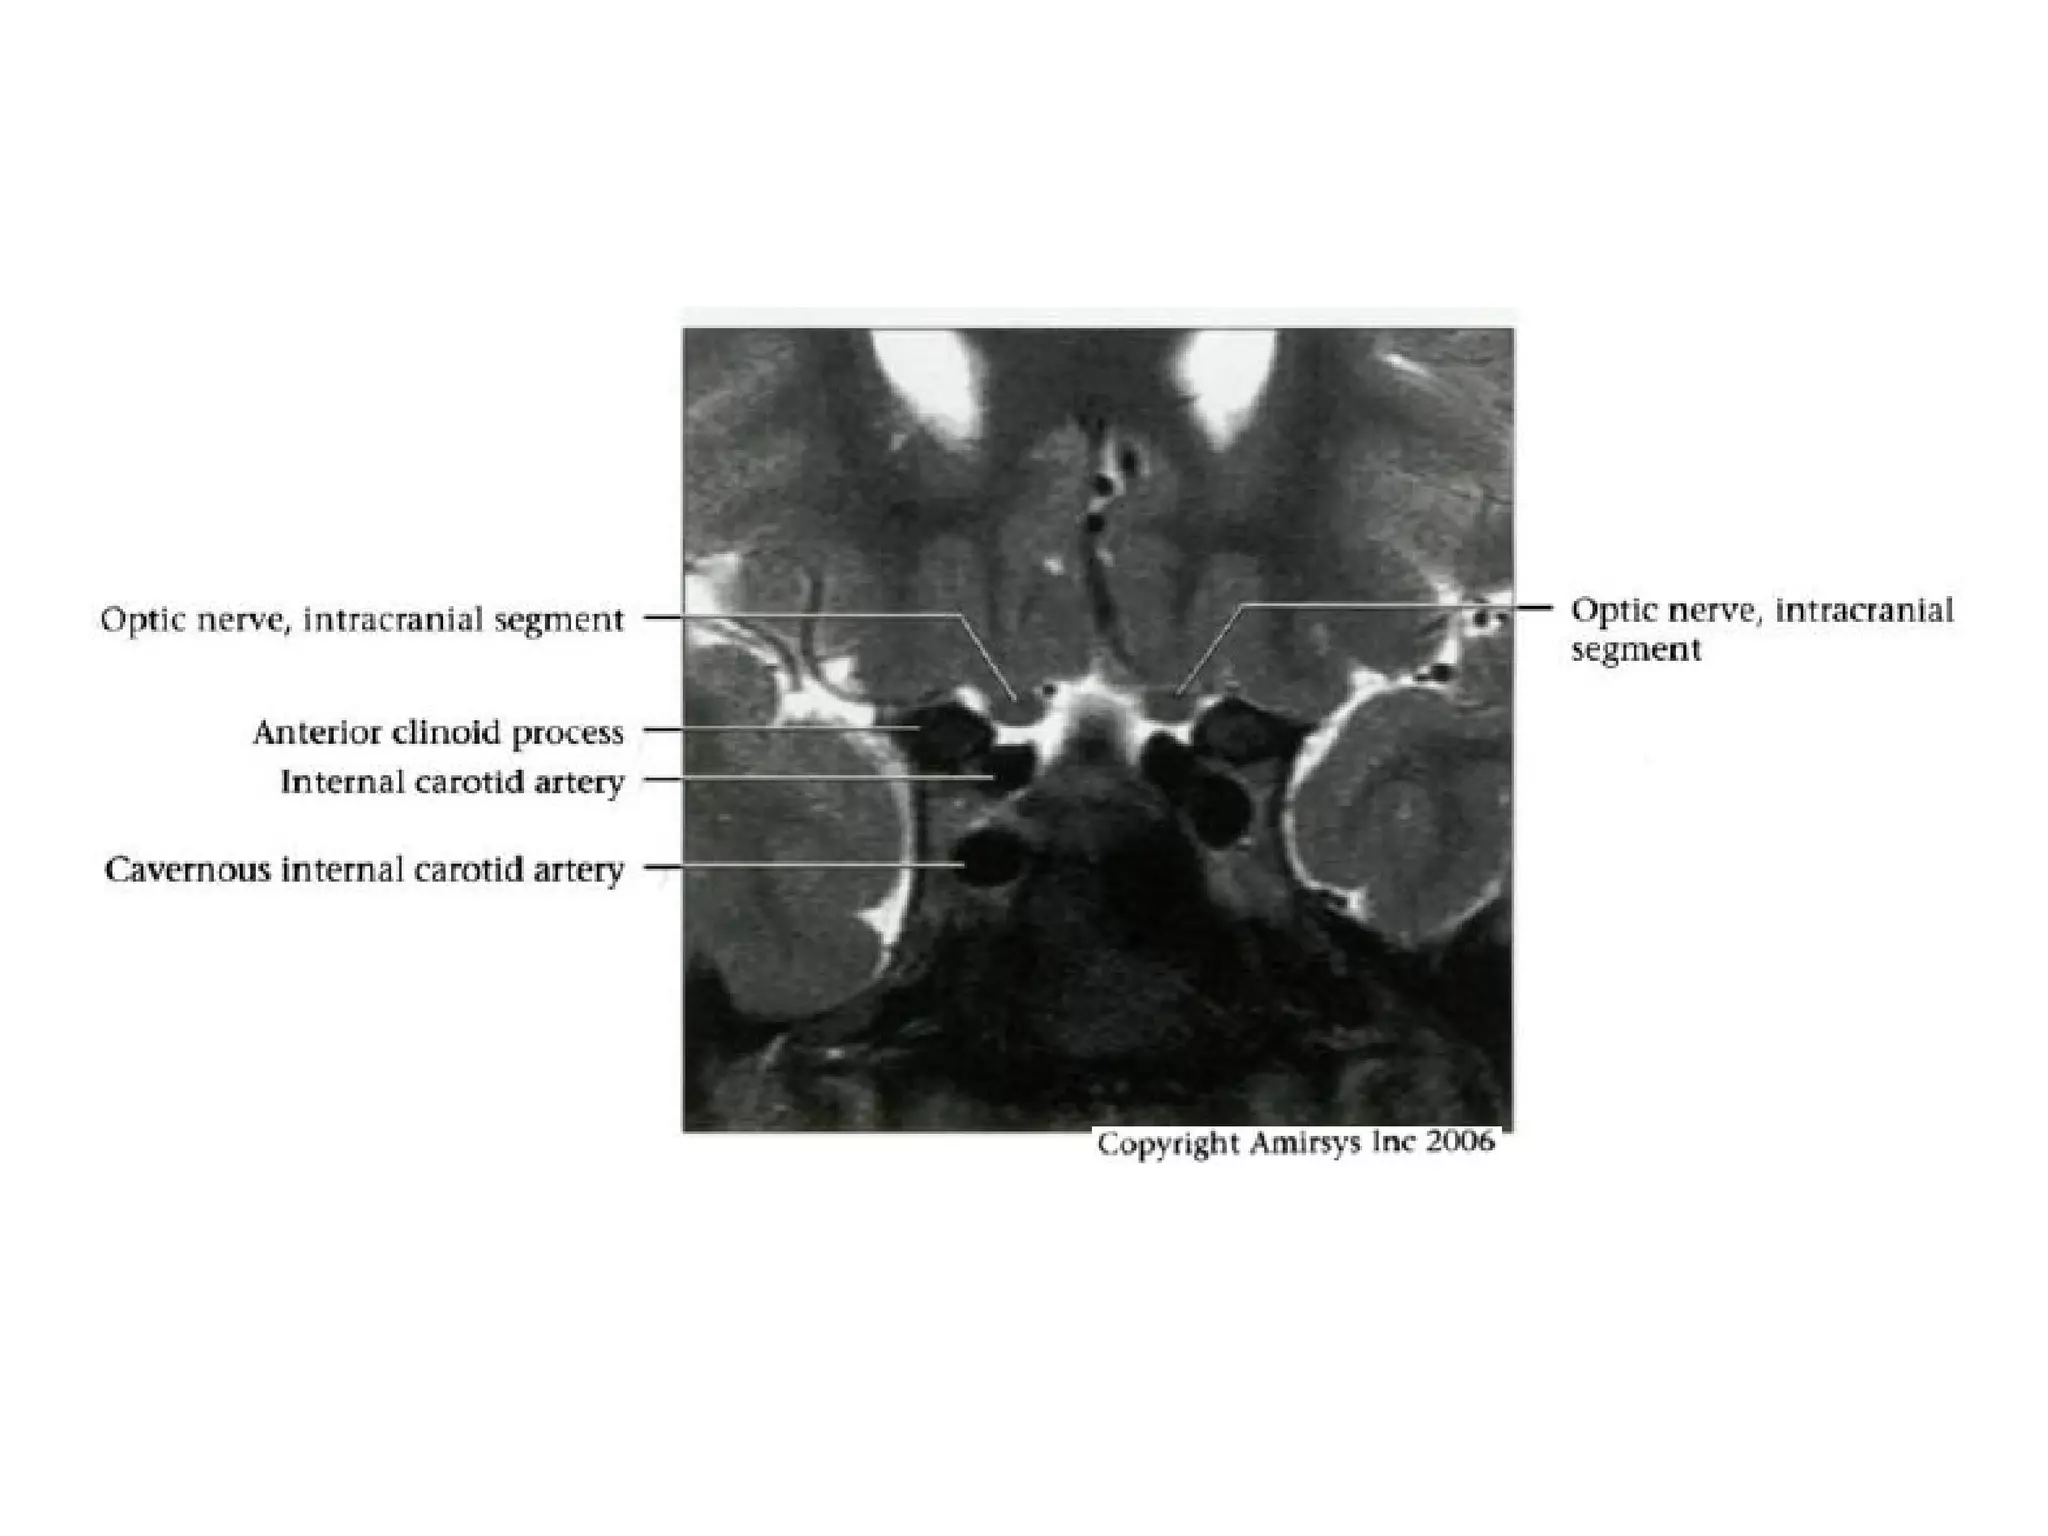

Intracranial segment

• About 10 mm length from optic canal to

chiasm

• Covered by pia and surrounded by CSF

within suprasellar cistern

• Ophthalmic artery runs inferolateral to

nerve

Cranial Nerve II:

The Optic Nerve

• Like the olfactory nerve, the optic nerve is a white-matter tract

without surrounding Schwann cells.

• It includes four anatomic segments: retinal, orbital, canalicular,

and cisternal.

• The retinal segment leaves the ocular globe through the lamina

cribrosa sclerae (the optic foramen of the sclera).

• The orbital segment, which is surrounded by a dural sheath

containing CSF, travels through the center of the fat-filled orbit.

• The canalicular segment is the portion that lies in the optic canal,

below the ophthalmic artery. This segment of the nerve is frequently

overlooked on radiologic images, so it should be specifically sought

when imaging for vision loss.

• Finally, the cisternal segment of the nerve can be visualized in the

suprasellar cistern, where the nerve leads to the optic chiasm. The

anterior cerebral artery passes over the superolateral aspect of the

cisternal segment of the nerve.

RadioGraphics 2009; 29:1045–1055

• Key anatomic landmarks in the suprasellar cistern

include the infundibulum (stalk) of the pituitary gland, the

anterior cerebral artery, and, posterior to the chiasm, the

mamillary bodies.

• The optic nerve terminates at the optic chiasm, where

the two nerves meet, decussate, and form the optic

tracts.

• The optic tracts travel around the cerebral peduncles,

after which most axons enter the lateral geniculate body

of the thalamus, loop around the inferior horns of the

lateral ventricles (Meyer loop), and enter the visual

cortex in the occipital lobe.